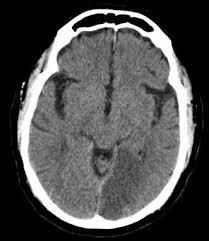

Causes of extra + subdural haemorrhages + likely patients + presentation?

Extradural = usually in young patients, due to head strike. Have lucid interval but then lose consciousness over few hours. Damage to middle meningeal artery or vein

Subdural = due to falls, no obvious cause - commonly in elderly + drunks - venous bleeding so presents slowly. Can be acute, subacute (3-7 days) or chronic (2-3 weeks)